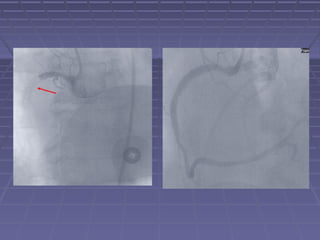

1990’s – Era of “Stent Mania”1990’s – Era of “Stent Mania”

JF

1990’s – Eraof “Stent Mania”1990’s – Era of “Stent Mania”